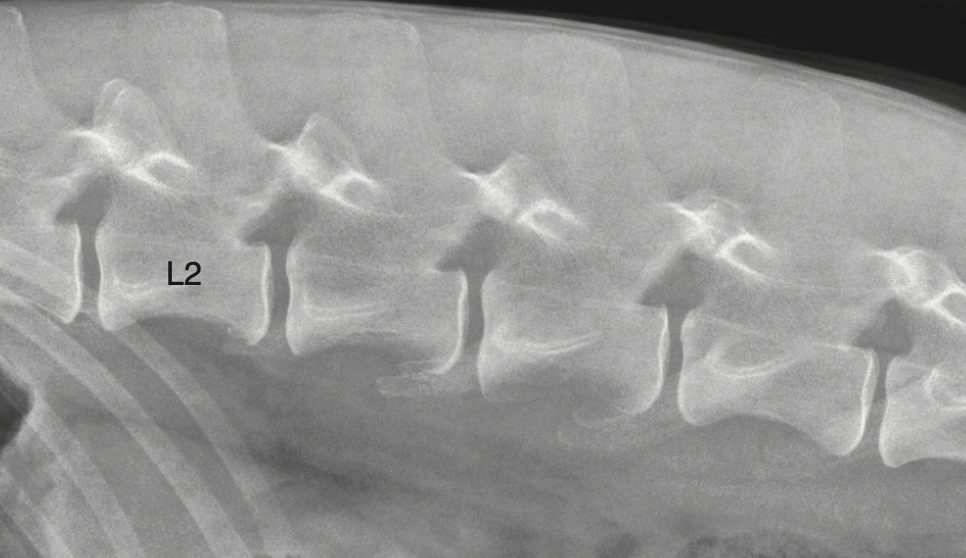

The pars lumbalis of the diaphragm attaches to which vertebrae in dogs?

C) L3 and L4

The right and left crura of the pars lumbalis attach to the cranial ventral border of L4 and the body of L3.

Where do the crura of pars lumbalis attach?

L3 body / L4 cranioventral border

Q

A